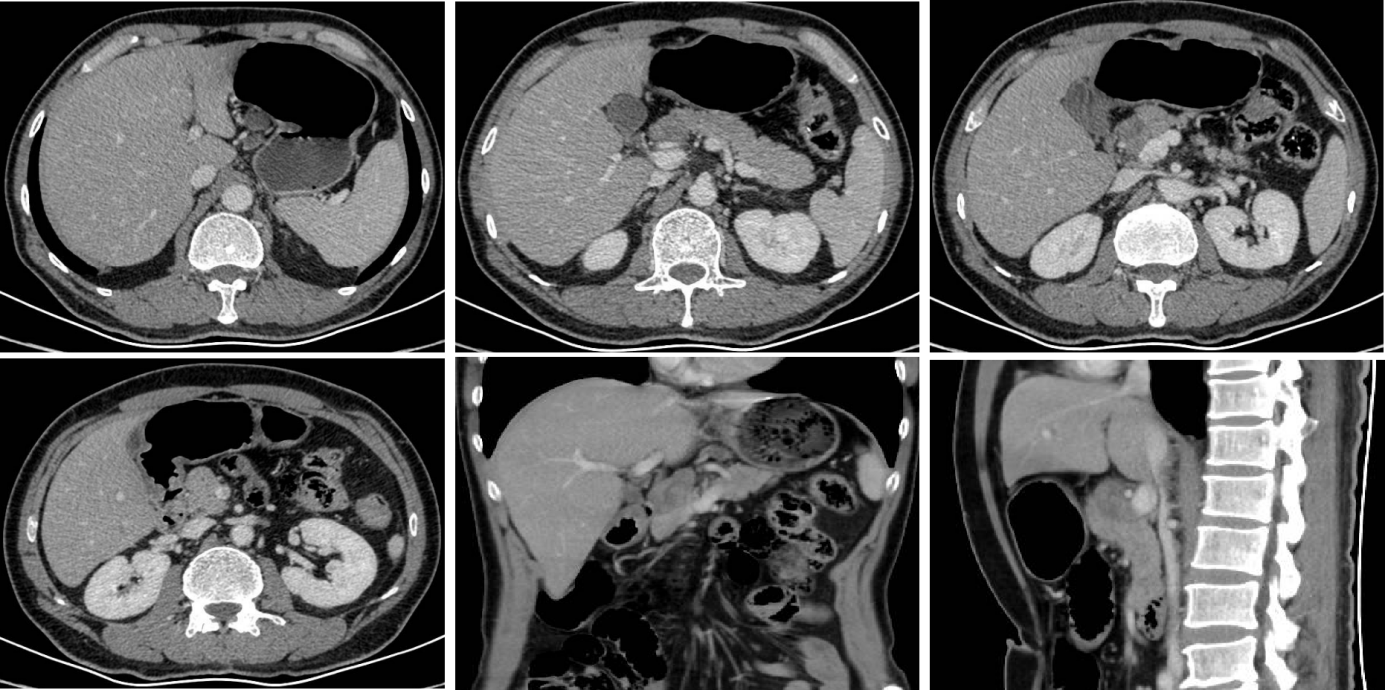

2024-04-12行第2周期行维迪西妥单抗+伦伐替尼+替雷利珠单抗治疗。2024-04-26、2024-05-03行第3周期行维迪西妥单抗+伦伐替尼+替雷利珠单抗治疗,过程中监测见患者AFP持续下降,2024-03-28为630.4ng/ml,2024-05-02为102.3ng/ml。期间于2024-04-24复查CT示:对比2024-03-12 腹盆部CT:胃窦部胃壁增厚大致同前,较厚仍约9mm,增强扫描强化明显。No.1-3,7-8,9组多发淋巴结部分缩小,较大原约46*31mm,现约25*22mm,与胰腺分界欠清。

2024-05-28再次复查CT示:对比2024-04-24腹盆部CT:胃窦部胃壁增厚大致同前,较厚仍约9mm,增强扫描强化明显。No.1-3,7-8,9组多发淋巴结部分缩小,较大原约25*22mm,现约14*13mm,与胰腺分界欠清(图3)。临床疗效评价:PR。

患者经过多种药物组合方案的尝试,并在二线更换抗HER2治疗ADC药物:维迪西妥单抗+仑伐替尼+替雷利珠单抗±卡培他滨,后逆转疾病进展趋势,AFP由最高点1546.07ng/ml将至最低60.34ng/ml。疗效评估由PD(PD)转化为PR(PR)。胰腺上方淋巴结节由46*31mm缩小为14*13mm,获得手术条件并成功手术。患者术后1年多复查未见肿瘤复发。